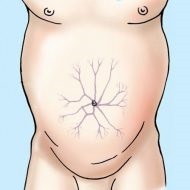

Kép: a megjelenése kompressziós szindróma

Coeliakia artéria kompressziós szindróma (KSCHS) a képen